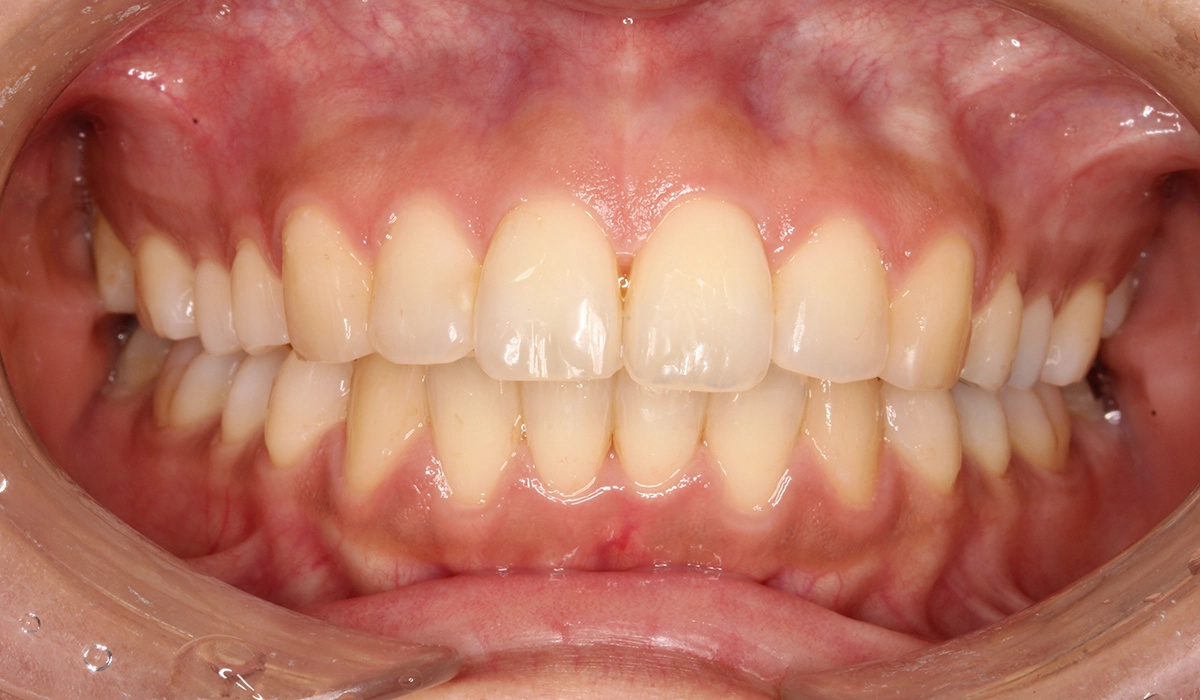

術後:正面

| 治療期間 | 18カ月 |

| 治療費用 | 990,000円(税込) |

| 治療内容 | 上下前歯部のがたつきを気にされており、検査後Ⅰ級叢生と診断いたしました。左上7番予後不良により抜歯し、左上8番を配列したためやや治療期間が長くなるも満足いく配列となり患者様も満足していただけました。 |